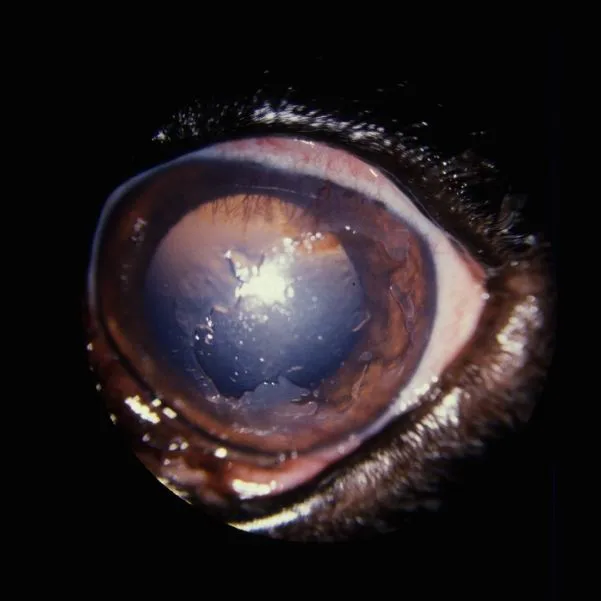

In this disease, the corneal epithelium sloughs off of the cornea, often leaving ragged epithelium along the edges of the ulcer (Figure A). The cause of this superficial erosion is unknown; however, it may be related to age or breed and is often spontaneous. While many clients suspect that a particular incident may be related to the start of these ulcers, the ulcers are often spontaneous and the suspected cause usually coincidental.

As the epithelium heals there will often be an intense vascular response, especially in certain breeds such as the boxer (Figure). I inform clients that the eye may become "ugly" red (like hamburger), but that the ulcer is healing and the patient will begin to keep the eye open with less squinting. The client should be informed that even after the current ulcer is healed, many patients are prone to getting future erosions in the same or opposite eye.